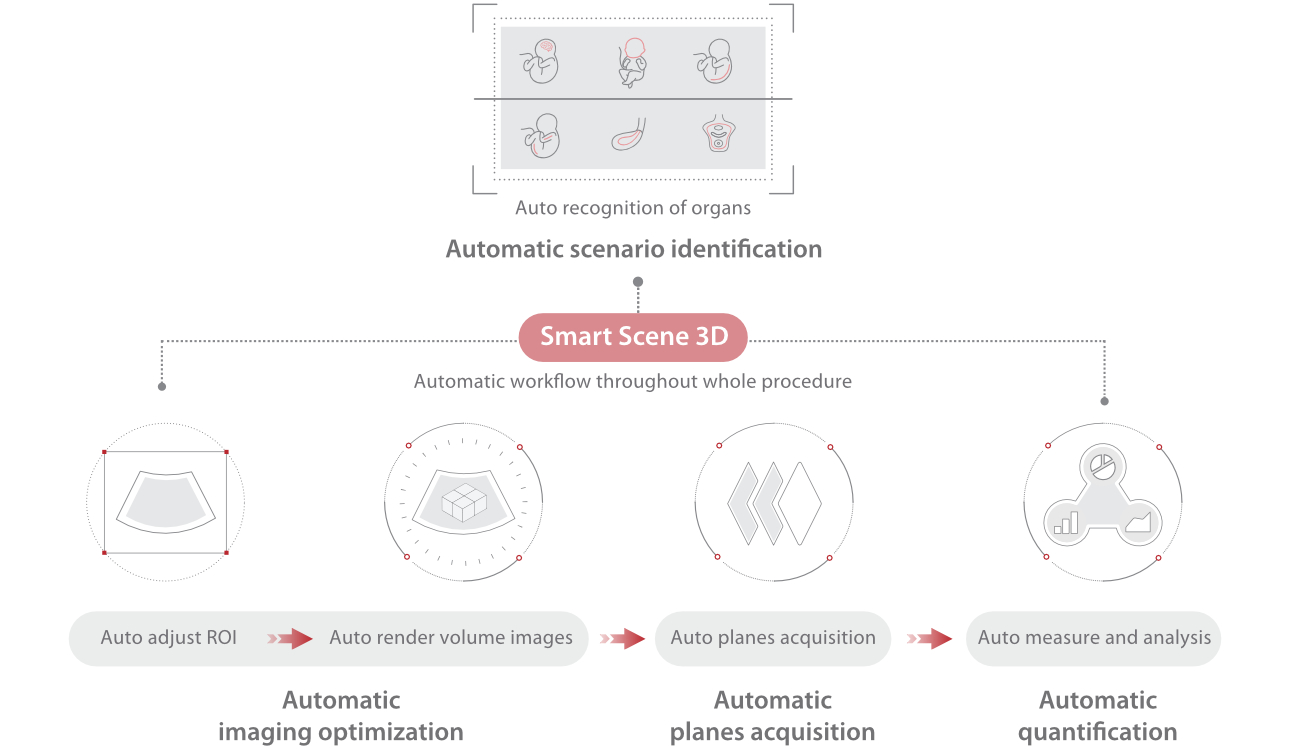

Le Nuewa?I9, con?u spÃĐcialement pour la santÃĐ de la femme et les soins nÃĐonataux, offre une expÃĐrience entiÃĻrement nouvelle gr?ce aux innovations dont il est dotÃĐ, tant à lâintÃĐrieur quâà lâextÃĐrieur. Ces innovations sont dÃĐveloppÃĐes sur la base d'une comprÃĐhension approfondie de scÃĐnarios cliniques complexes, fournissant des rÃĐponses prÃĐcises et adaptÃĐes ainsi qu'une efficacitÃĐ exceptionnelle et une expÃĐrience utilisateur remarquable.

Solution complÃĻte gr?ce au ZST +

La plate-forme ZST+?est une innovation extraordinaire, reprÃĐsentant une ÃĐvolution de lâimagerie ultrasonore. Elle transforme la formation conventionnelle de faisceaux en un traitement basÃĐ sur les canaux de donnÃĐes. Elle repousse les limites de lâimagerie conventionnelle et du compromis entre rÃĐsolution spatiale, rÃĐsolution temporelle et uniformitÃĐ tissulaire en offrant une qualitÃĐ dâimage exceptionnelle pour des solutions dâimagerie infinies et en constante ÃĐvolution.